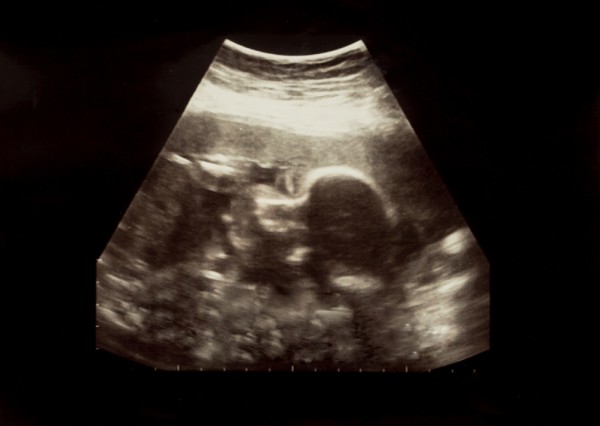

Узи на 27 неделе

Скорее всего, плановое ультразвуковое исследование уже прошло. Однако врач может рекомендовать повторное обследование на 27-й акушерской неделе беременности. Обычно это необходимо в случае перенесённых инфекционных заболеваний у будущей мамы, подозрений на патологии беременности или задержки в развитии плода.

По УЗИ специалист может оценить:

- Положение плода.

- Степень зрелости плаценты, которая должна быть равной 0. Также исследуется её расположение.

- Сердечный ритм ребенка, составляющий примерно 140-150 ударов в минуту.

- Процесс развития и роста малыша для выявления возможной задержки внутриутробного развития.

- Состояние, толщина и размеры матки.

Кроме того, врач оценивает количество и качество околоплодных вод. Нормальным объемом считается примерно 1-1,5 литра. Если объем превышает 3 литра, это состояние называется многоводием. Объем менее 500 мл указывает на маловодие. При обнаружении таких отклонений врач назначает соответствующее лечение.

Если на предыдущих ультразвуковых исследованиях пол малыша не был установлен, то на 27-й неделе беременности врач сможет его определить.